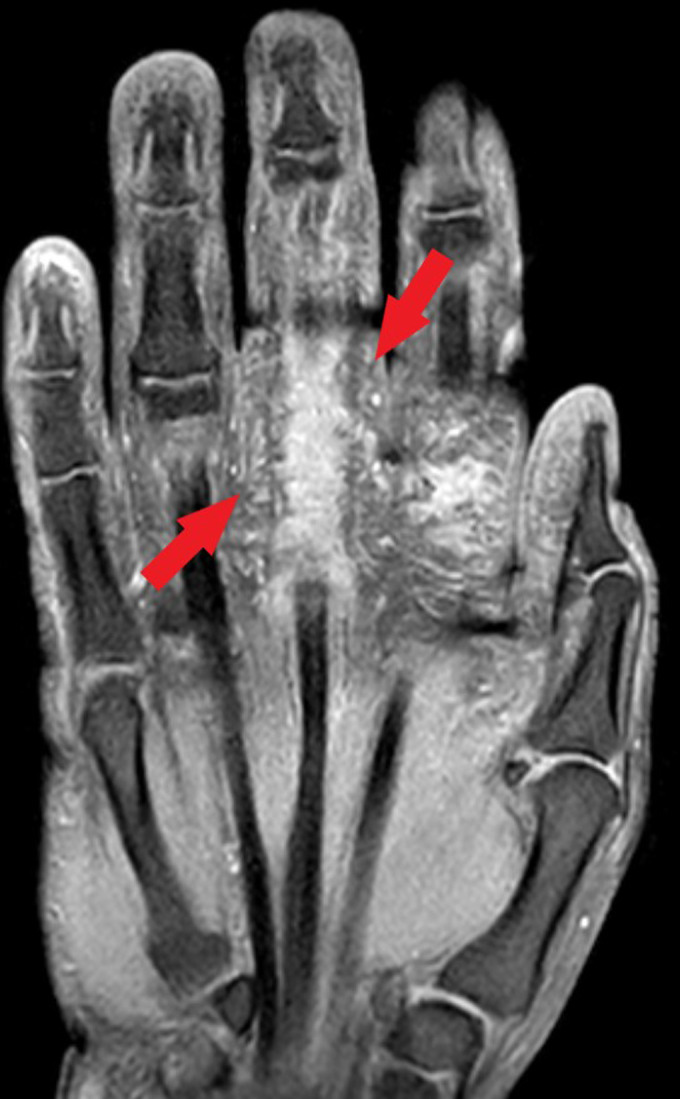

Sarcoidosis, an inflammatory disease characterized by non-caseating granulomas of unknown etiology, typically manifests with pulmonary involvement. However, presentations without pulmonary manifestations are exceedingly rare. We present 2 cases illustrating unusual presentations of sarcoidosis without pulmonary involvement. A 60-year-old male presented with chronic joint pain and swelling in the left hand. Despite recurrent hospital visits and inconclusive evaluations, granulomatous tenosynovitis was confirmed through histopathological examination. Systemic involvement was ruled out, and the patient responded well to corticosteroid therapy. A 36-year-old female exhibited persistent subcutaneous nodules on the left hand for 6 years. A biopsy confirmed non-caseating granulomas consistent with sarcoidosis. Despite the absence of pulmonary findings, systemic screening revealed no further involvement. Intralesional corticosteroid therapy yielded significant improvement. Although sarcoidosis typically presents with pulmonary involvement, cases without pulmonary manifestations are rare. Our cases highlight the diagnostic challenges and delayed recognition of such presentations. Increased awareness of atypical presentations is crucial for timely diagnosis and management to prevent potential systemic complications.